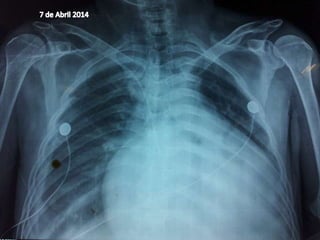

B (Ventilacion)

Tórax en tonel, Polipneico 45 resp. x

min. Disociación toraco abdominal.

Con saturación al 85%

Uso de músculos intercostales.

Estertores bilaterales subcrepitantes.

Disminución del claro bilateral.

Se aporta O2 mascarilla con

reservorio a 10 litros por minuto. Con

Saturación al 99%.

7 de Abril del 2014 hora:00:00 hrs